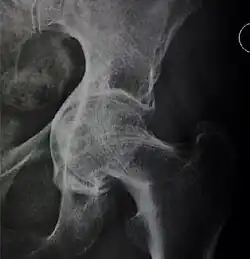

X-ray of hip dysplasia

X-rays of hip dysplasia are one of the two main methods of medical imaging to diagnose hip dysplasia, the other one being medical ultrasonography.[1][2] Ultrasound imaging yields better results defining the anatomy until the cartilage is ossified. When the infant is around 3 months old a clear roentgenographic image can be achieved. Unfortunately the time the joint gives a good x-ray image is also the point at which nonsurgical treatment methods cease to give good results.